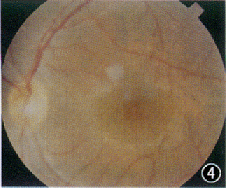

患者男,21岁。因双眼视力逐渐下降7年,蛋白尿、听力下降4年,高血压1年,于1998年5月入我院肾病内科诊治。既往无眼部疾病史。母亲曾有“肾盂肾炎”病史,已治愈。其他家族病史不详。体检:血压160/110 mm Hg(1 mm Hg=0.133 kPa);轻度Cushing征外貌,余无异常。眼部检查:裸眼视力右眼0.2,左眼0.4;矫正视力右眼0.7(-11.0 DS +0.75 DC×90°),左眼0.7(-10.0 DS +0.75 DC×90°);双眼晶状体前表面中央区局限性前突,呈锥形,囊膜下可见小斑点状白色混浊(图1,2);双眼视盘色泽正常,边界清晰,视网膜血管大致正常,后极部黄斑区周围可见散在的黄白色点状颗粒,黄斑中心窝反光可见(图3,4);眼底血管荧光造影检查示双眼黄斑拱环结构破坏。辅助检查:(1)耳科电测听:双耳对称性感音神经性耳聋(中、重度);(2)肾活检报告:光镜示系膜增殖性肾小球肾炎改变(重度);免疫荧光检查为阴性;电镜示肾小球基底膜广泛变厚、劈裂;(3)眼电图、视网膜电图未见异常表现;(4)尿蛋白50 mg/L,血尿素氮 7.2 mmol/L, 血清肌酐185.6 μmol/L。诊断:Alport综合征。

图1 右眼晶状体前表面中央区局限性前突,呈锥形,囊膜下可见小斑点状白色混浊(箭头) 图2 左眼晶状体前表面特征同图1 图3右眼视盘色泽正常,边界清晰,视网膜血管大致正常,后极部黄斑区周围可见散在的黄白色点状颗粒,黄斑中心凹反光可见 图4 左眼眼底特征同图3